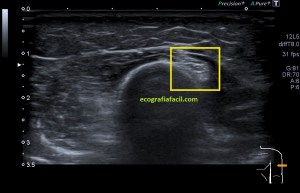

La anatomía locorregional es siempre importante, te dejo en la imagen 3 una muestra de aquella que es más importante para que intentes, en caso de que estés empezando, a reproducir dicha imagen. Ojo que la vesícula no suele estar colocada siempre tan bonita para que la veamos y hay que trabajársela, como truco, prueba a poner al paciente en decúbito lateral izquierdo.